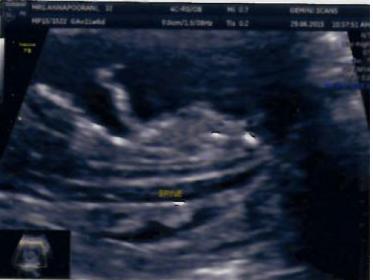

Now I got clear pics of 12W, 16W & 20 W.

Pls predict.

16 W imagesAttachment 28068Attachment 28069